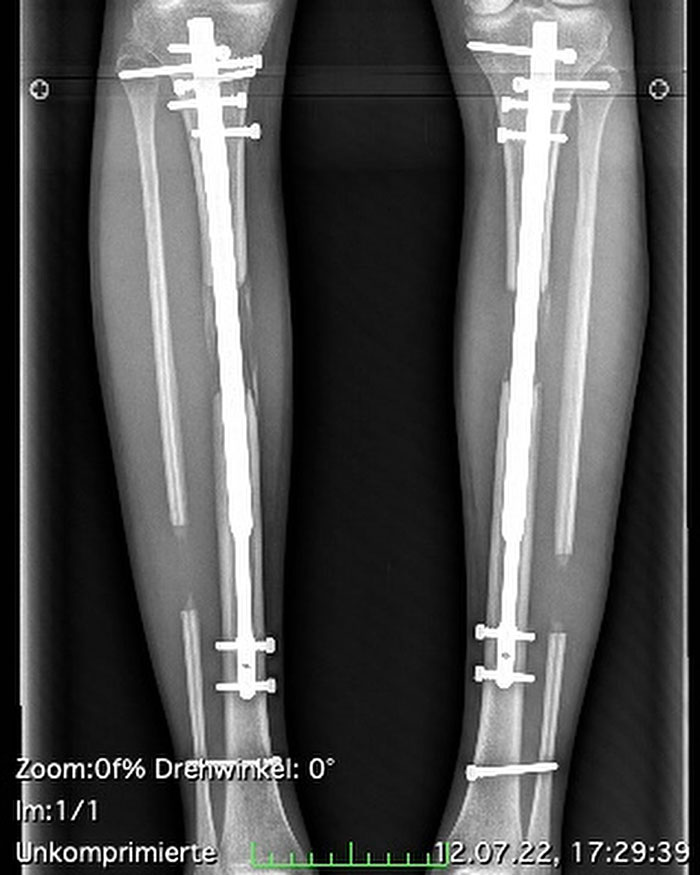

After the operations, during which Theresia’s bones were split and stabilized with metal rods, she suffered from bone infections twice.

The TV star reported said: “When I had to run a little or be faster – it’s just strange to run with metal in your legs.”

Now, Theresia longs for the day when the metal support rods can be removed, saying: “I’m longing for that day when these rods finally come out,” The Daily Mirror reported.

Or an internal rod: this newer option is a screw-like device that your surgeon places inside the bone. This device isn’t visible outside the body.

Specialists typically separate the bones by a total of one millimeter per day. If the patient has external fixators, the patient or a caregiver turns screws or dials on the fixator to achieve the required daily separation.

If the patient has intramedullary nails (magnetic nails), the patient uses a remote control to activate the internal magnet, causing the nail to elongate.